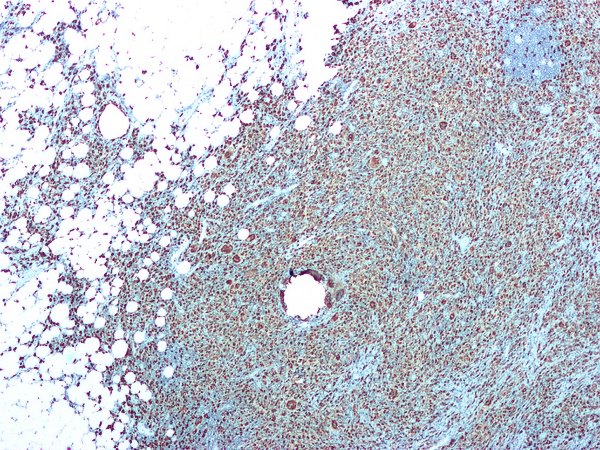

В группе хронического пиелонефрита при анализе материала биопсий коркового вещества почки различают 6 морфологических вариантов. Нет достаточных оснований рассматривать все из них как последовательные стадии изменений — правильнее считать их неодинаковыми формами течения хронического пиелонефрита[5], обусловленными различиями факторов, способствующих развитию пиелонефрита.